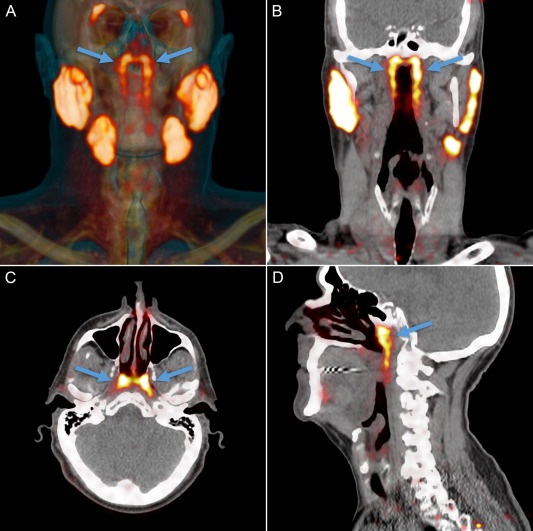

Четвертая пара слюнных желез расположена в геометрическом центре черепа, ближе к его основанию. Фото: thegreenjournal.com

Медики обнаружили в организме человека четвертую пару крупных слюнных желез  - органа, о существовании которого ранее никто не подозревал. Ученые назвали эти железы tubarial (трубными). Они находятся почти в геометрическом центре черепа, ближе к его основанию. Вероятно, из-за такого расположения железы до сих пор оставались незамеченными. Любопытно, что это первое подобное открытие за последние 300 лет пишет Radiotherapy and Oncology.

Исследователи для обнаружения и визуализации опухоли в организме взяли меченую радиоактивными изотопами глюкозу. Специалисты обнаружили, что глюкозу поглощали не только опухоли, но и некие органы, которые и оказались четвертой парой слюнных желез.

Как выяснили медики, четвертая пара слюнных желез отвечает за смазку и защиту носоглотки и зева.